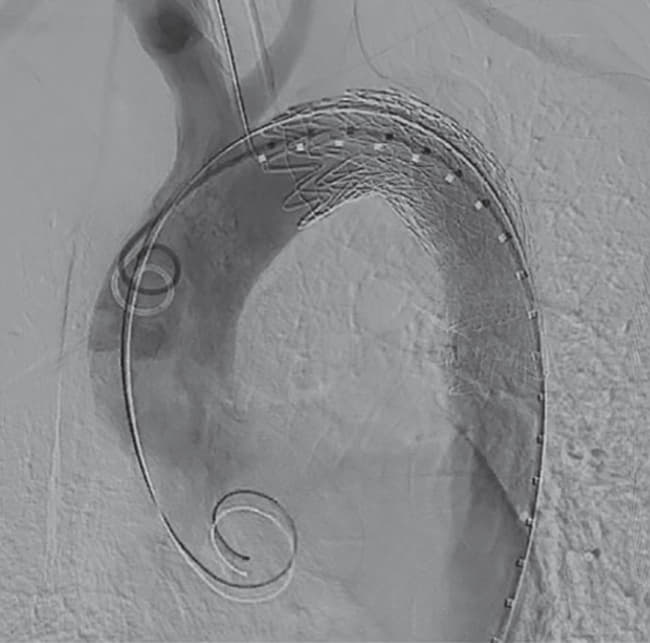

全身麻酔下、仰臥位にて手術を開始した。右鼠径部を切開し、右総大腿動脈をテーピング、タバコ縫合をおいた。ヘパリン投与後、右総大腿動脈から5 Frシースを挿入した。右総大腿動脈シースからピッグテールカテーテルを上行大動脈まで進め、ステントグラフト用ガイドワイヤーに変更、シースを20 Frゴア® ドライシール フレックス イントロデューサシースに入れ替えた。デバイスは末梢側からTAG® コンフォーマブル ステントグラフト28 mm × 10 cm、および31 mm × 10 cmを選択した。まず28 mm × 10 cmを左鎖骨下動脈末梢から留置、ついで31 mm × 10 cmを予定留置部位まで進め、造影で左総頚動脈および左鎖骨下動脈の位置を確認し、アンギュレーションコントロールダイヤルをゆっくり回しながらデバイス中枢の角度を慎重に大動脈に合わせた後に留置した。解離症例であるためバルーンによる圧着は施行せず、最終造影でエンドリークを含め異常のないことを確認し手技を終了した。手術時間は1時間11分であった。

TAG® コンフォーマブル ステントグラフトは従来のコンフォーマブル TAG® ステントグラフトに改良を加え、デバイスの中枢側の角度調整ができるよう工夫がされているため、急峻な弓部大動脈に対しても追従することが期待できる。特にZone 2症例に対しては、今までのデバイスであればどうしても小弯側が追従できず飛び出てしまい、これによるbird beakが問題となっていたが、TAG® コンフォーマブル ステントグラフトであれば、中枢ネック部に対しデバイスを大動脈に平行に留置することを意図したアンギュレーションコントロール機能を有するため、bird beakのリスク低減が期待でき、かつ大弯側のシーリングゾーンも有効に利用できるようになった。手技上の注意点としては、アンギュレーションコントロールダイヤルを回転させてから中枢の角度が変わるまでにタイムラグがあること、また一旦角度を曲げると元には戻せないことから、この部分の手技に対しては、数回アンギュレーションコントロールダイヤルを回し、一呼吸おいて画像をしっかり確認しながら行うことが肝要である。